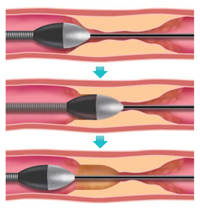

ダイヤモンドバック

先端にあるダイヤモンドで構成されたクラウンが軌道回転して石灰化を削ることができます。大きな石灰化プラークを有する病変に有用です。

病変に応じてロータブレーターと使い分け/組み合わせて使用します。

削ることが可能